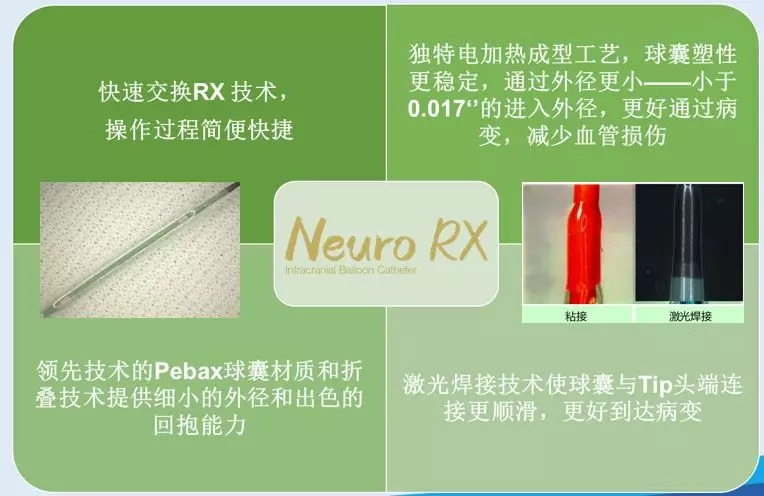

赛诺 2.0*15mm球囊扩张

赛诺 2.0*15mm球囊扩张